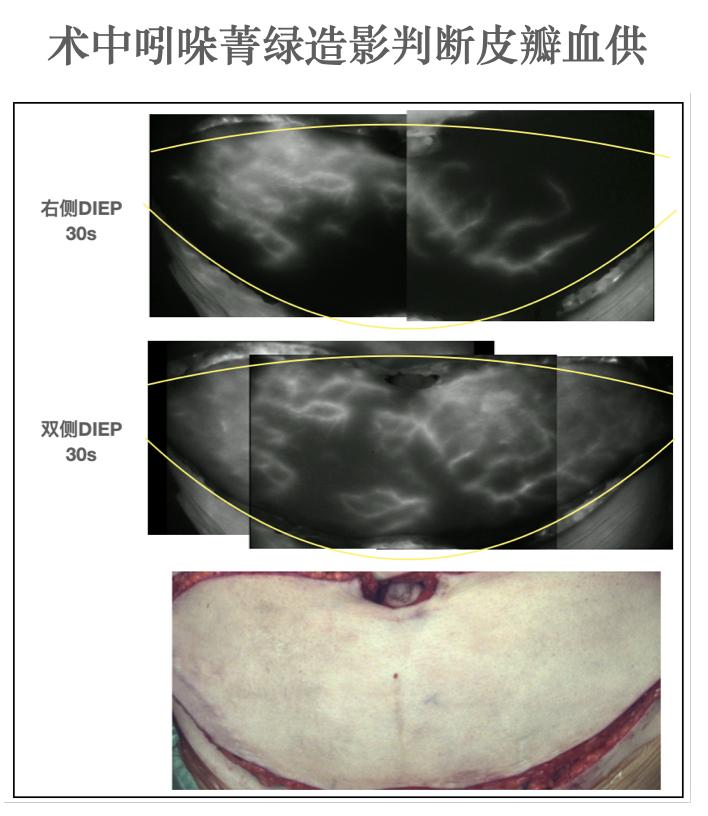

手术前进行了必要的CT血管造影、淋巴核素显像、胸三维扫描,提前预判手术关键点、模拟术后效果。术中在SPY荧光皮瓣造影和激光多普勒血流显像技术的辅助下,在保证血供的前提下,转移的皮瓣长约41cm,宽约15cm,范围相当大,总重量达到了970g。(图2、图3、图4)术中吻合接通了两组动脉和静脉,二维平面的肚皮肉肉塑形后趋于正常乳房半球形的三维形态,腋窝在瘢痕松解和皮瓣填充后,凹陷明显改善。

术中使用ICG造影技术判断皮瓣血供良好

图3 术中使用ICG造影技术判断皮瓣血供良好